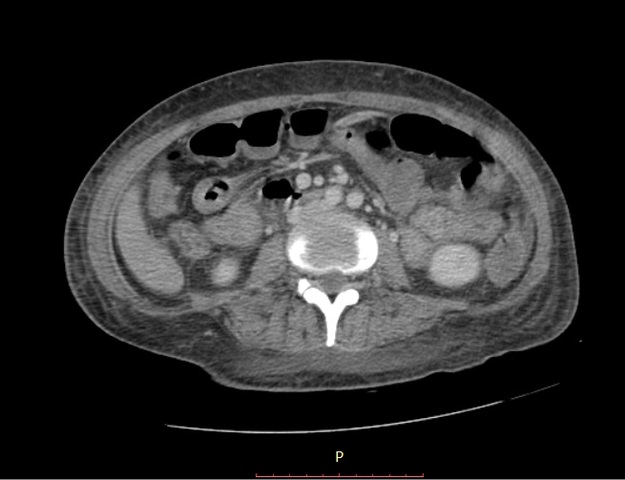

TAC TAP

RESULTADOS AL MOMENTO NEGATIVOS VERIFICADOS EN SISTEMA.